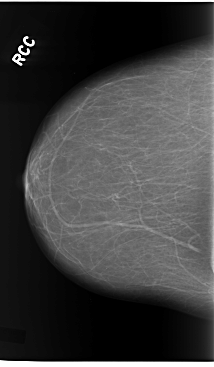

C_0119_1.RIGHT_CC

RIGHT_CC LINES 5864 PIXELS_PER_LINE 3424 BITS_PER_PIXEL 12 RESOLUTION 50 NON_OVERLAY